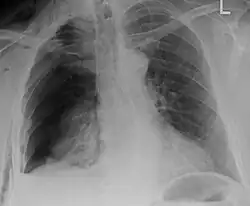

| An X ray showing multiple old fractured ribs of the person's left side as marked by the oval | |

Plain X-rays often pick up displaced fractures but often miss undisplaced fractures.[13] CT scanning is generally able to pick up both types of fractures.[13]

Right sided pneumothorax and rib fractures -